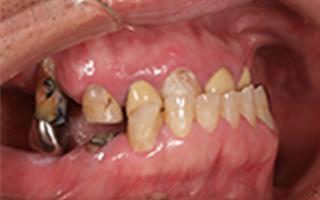

Before

After

| 55歳 男性 | |

|---|---|

| 主訴 | 前歯でしか咬めなく、食事を摂るのに非常に困難で辛い |

| 処置内容 | 上顎6本、下顎3本 |

| 治療費用 | 上顎: 約230万(税込) 下顎: 約120万(税込) |

| 治療期間 | 上顎: 1年(仮歯まで8ヶ月) 下顎: 8ヶ月(仮歯まで5ヶ月) |

| リスク | 上部構造物、仮歯の破折、術後の腫れ(3日)、人工歯根脱落リスクがあります |